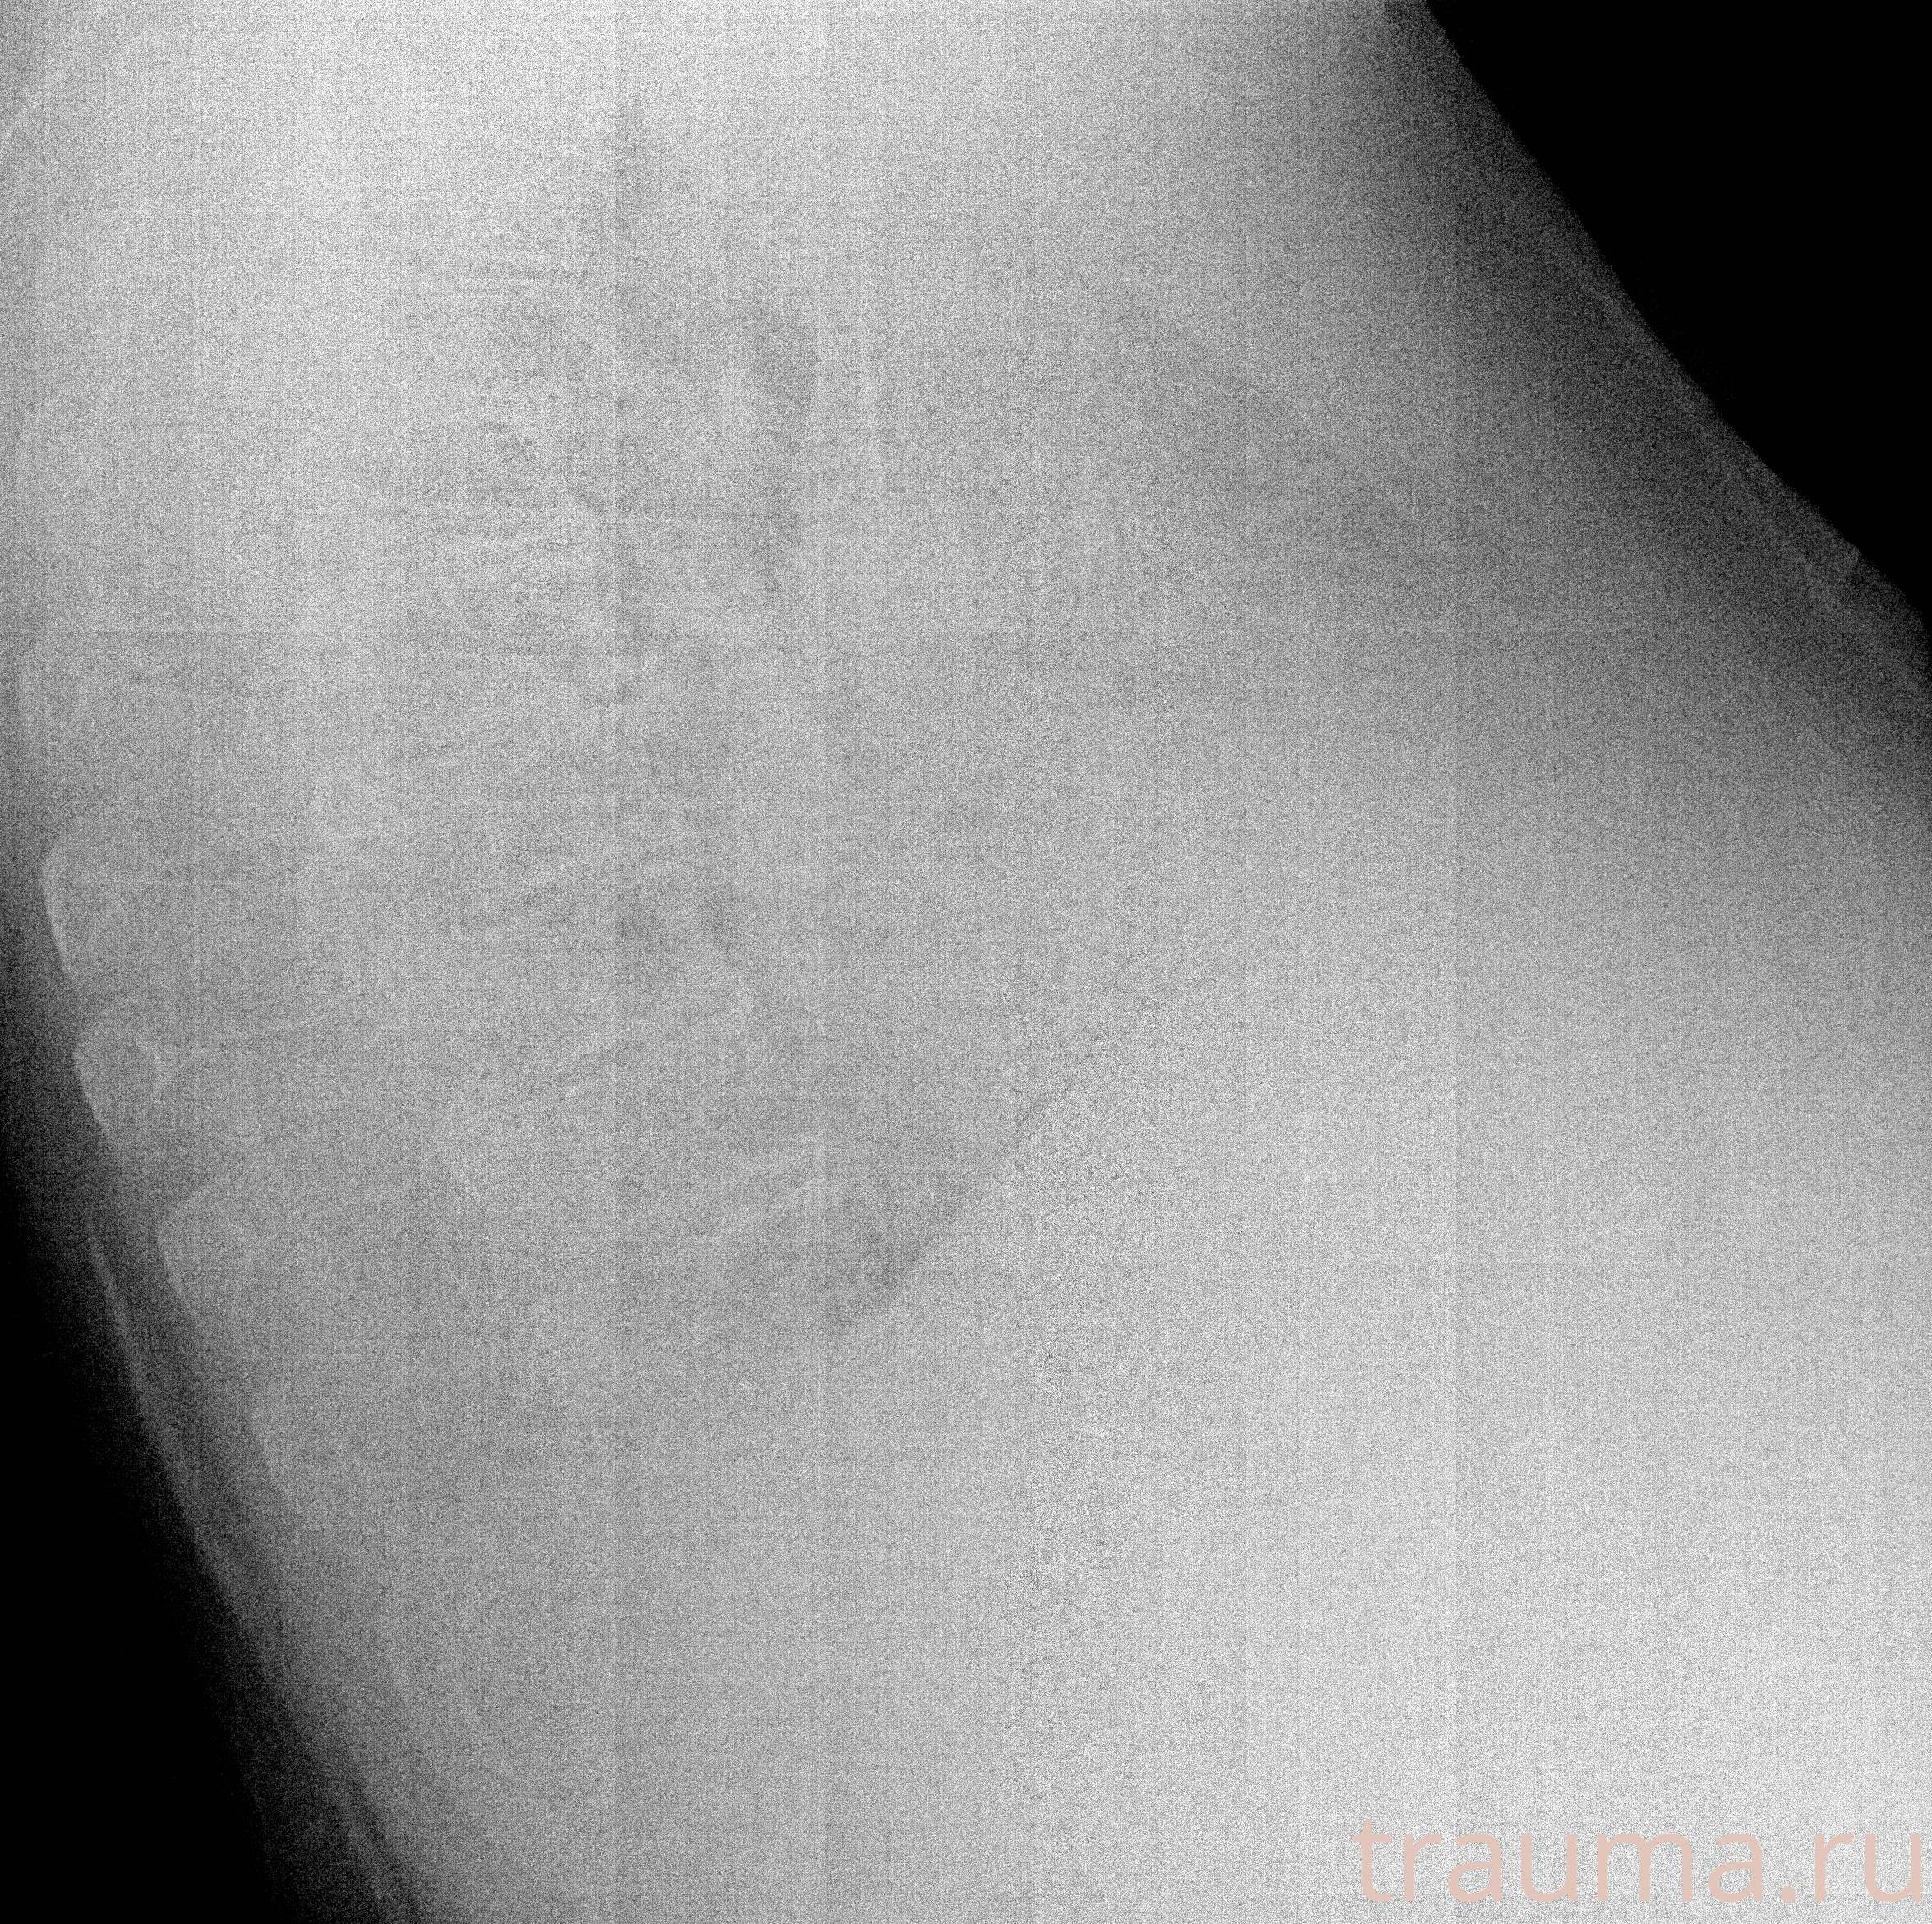

Рентген на дому: по вашему адресу приезжает врач-рентгенолог, травматолог-ортопед с мобильным рентгеновским аппаратом, проводит диагностику травмы или заболевания, делает необходимые рентгенограммы, дает рекомендации по дальнейшему лечению. Получить качественные снимки в домашних условиях возможно благодаря уникальной методике, разработанной МосРентген Центром для института  Склифосовского